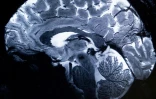

Le champ magnétique de cet aimant hors norme atteint 11,7 T (tesla), permettant l'obtention d'images 10 fois plus précises que celles produites actuellement dans les hôpitaux, où la puissance des IRM ne dépasse pas 3 tesla.

Sur l'écran d'Alexandre Vignaud, des images de coupes de cerveau sont comparées avec ce qu'aurait donné un IRM de 3 ou 7 tesla:

"Avec cette machine, on peut voir les tout petits vaisseaux qui alimentent le cortex cérébral ou des détails du cervelet qui étaient quasi invisibles jusqu'alors", commente-t-il.